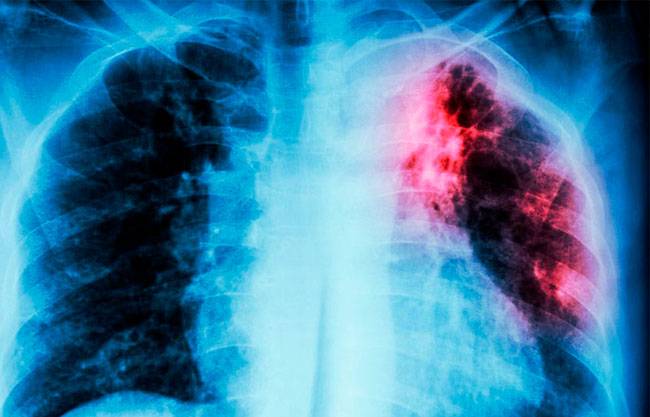

Saltillo, Coah.- Durante la temporada invernal, la tuberculosis es una de las enfermedades que se mantiene bajo vigilancia epidemiológica en Coahuila , ya que en promedio se llegan a detectar hasta 700 casos por año.

Martha Alicia Romero, directora de Prevención y Promoción a la Salud, detalló que este año la cifra ha descendido con respecto a los casos del 2024, pues hasta el cierre de noviembre se tienen contabilizados 588.

“ La tuberculosis se ha mantenido entre el mismo número de casos, desde hace mucho tiempo, y las recomendaciones que le damos a la población, es que el que se identifique con una tuberculosis, debe de darse un seguimiento a ella y a todos sus contactos, tengan o no tengan síntomas se les hace un estudio”, reiteró.

Explicó que la presencia de una tos persi